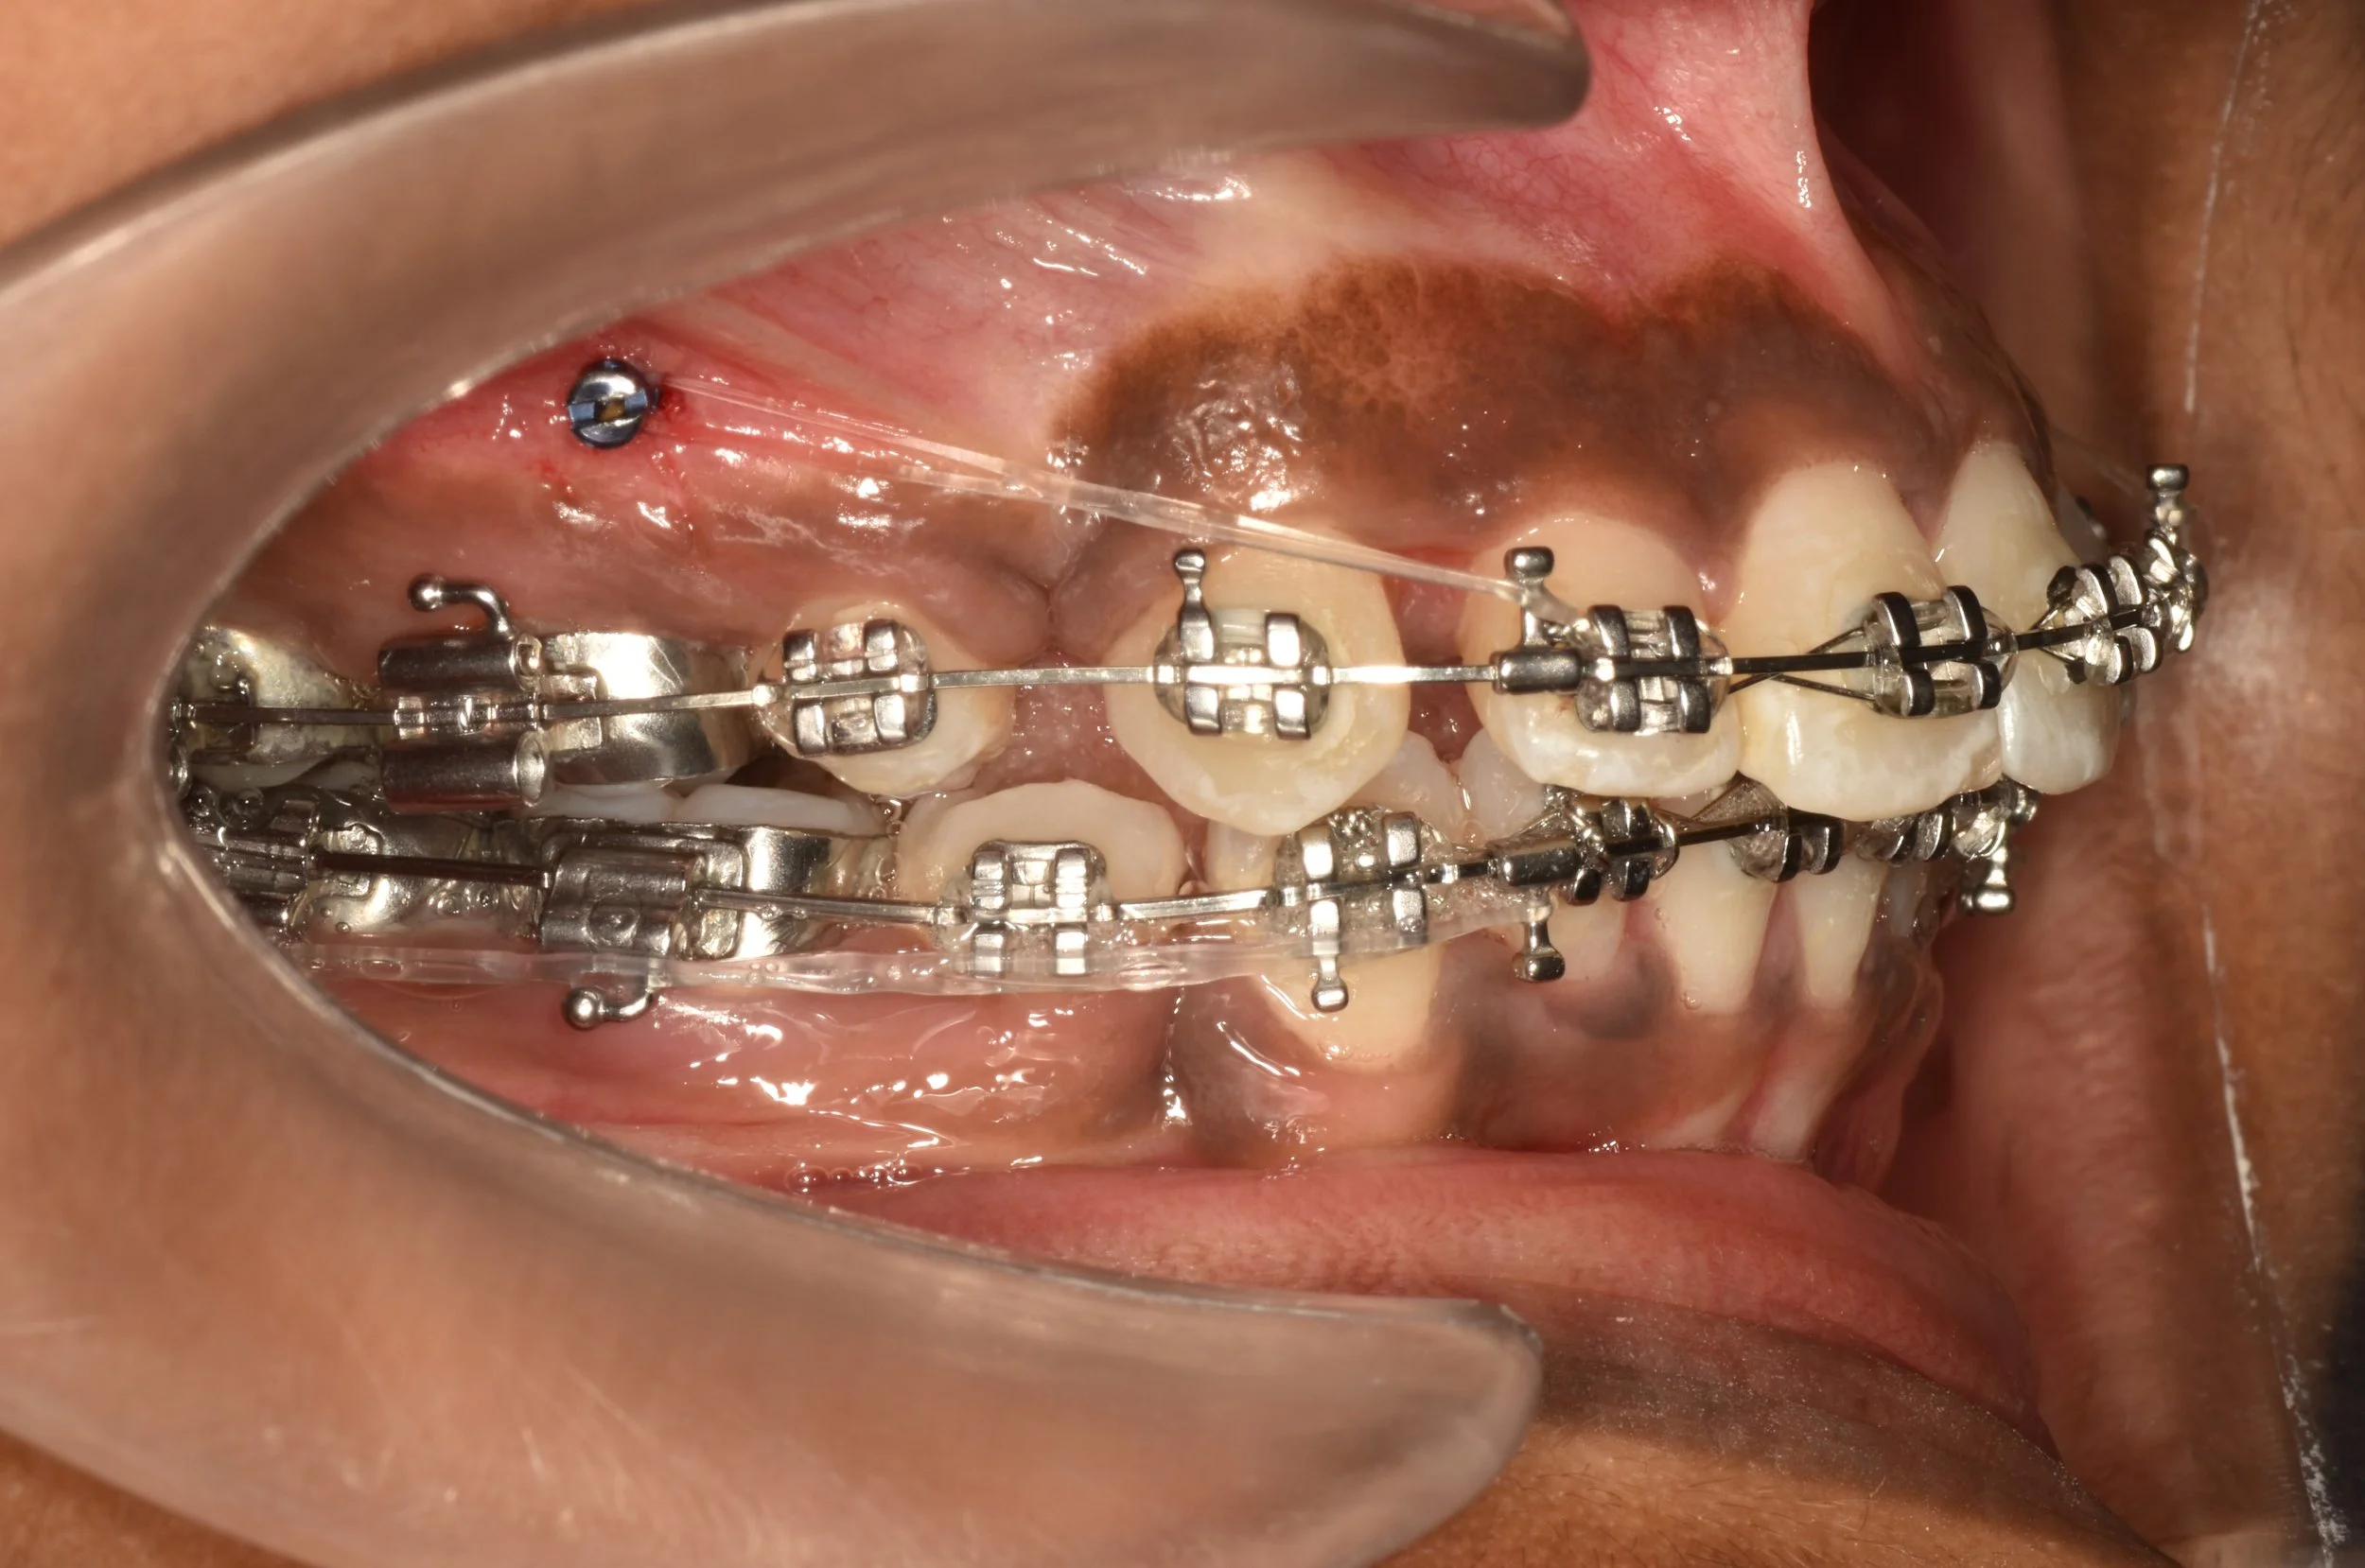

Extra-radicular implants